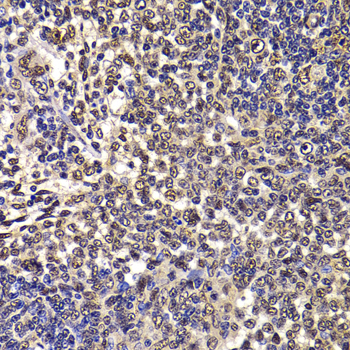

Immunohistochemistry of paraffin-embedded rat spleen using WBSCR22 antibody at dilution of 1:100 (x40 lens).